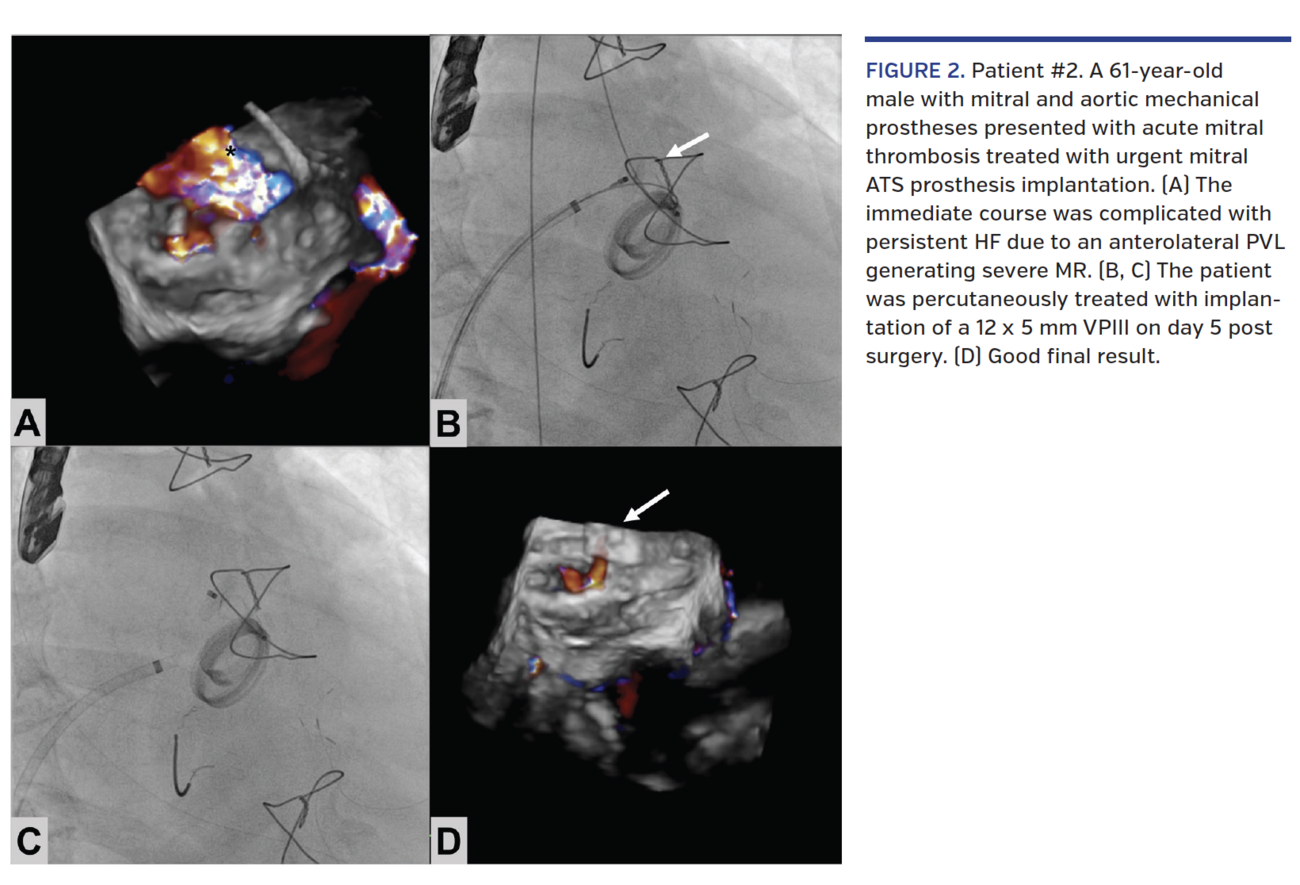

Patient #2. A 61-year-old male with mitral and aortic mechanical prostheses presented with acute mitral thrombosis (Video 3) treated with urgent mitral ATS prosthesis implantation (ATS Medical). The immediate course was complicated with persistent HF due to an anterolateral PVL generating severe MR (Figure 2A and Video 4) that was percutaneously treated with implantation of a 12 x 5 mm VPIII on day 5 post surgery (Figures 2B and 2D; Video 5).